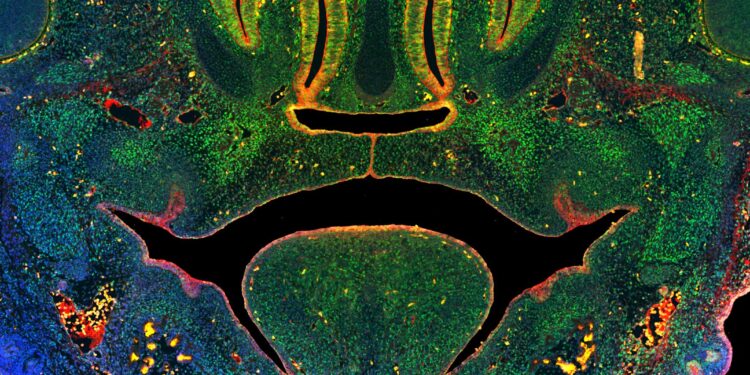

This image of a cross-section of the mid-face of a mouse embryo illustrates the fusion of tissues that form the secondary palate above the tongue. Green coloring illustrates cells expressing a key enzyme involved in DNA methylation, blue indicates nuclei of all cells, red indicates epithelial cells. Credit: University of Wisconsin-Madison

Published in the Proceedings of the National Academy of Sciences (PNAS), the study provides the first direct evidence of a mechanism called DNA methylation, which is necessary for craniofacial development. DNA methylation is a process by which a group of molecules are added to DNA to change gene expression without actually altering the DNA sequence. It is also affected by various environmental factors. Researchers found that disrupting DNA methylation interferes with the development of the lip and palate and causes these birth defects in mice.

His team’s work has confirmed the essential role of DNA methylation in the regulation of orofacial development during embryonic development and demonstrates how disruptions of this process modify the ability of stem cells to form the connective tissue of craniofacial bone and cartilage, thus leading to the appearance of OFC.